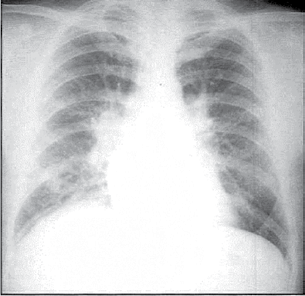

Paciente do sexo feminino, 39 anos, asmática, tem antecedente de valvopatia mitral reumática e estava assintomática até aproximadamente há 1 mês, quando passou a apresentar sintomas de dispneia em repouso e sensação de palpitação taquicárdica arrítmica. Procura atendimento médico por conta do cansaço intenso e o exame físico evidencia: taquidispneia em repouso, FC=pulso=120 bpm, PA = 120x80 mmHg, estertores crepitantes em 1/2 inferior de ambos os pulmões, associados a sibilos expiratórios, bulhas arrítmicas em 2 tempos, com sopro diastólico em foco mitral (ausculta dificultada pela alta frequência cardíaca). A radiografia de tórax e o eletrocardiograma dessa paciente encontram-se ilustrados a seguir.

O mecanismo fisiopatológico que melhor explica a descompensação clínica dessa paciente é

Leia o enunciado a seguir e responda às questões de números 04 e 05.

A melhor abordagem terapêutica inicial consiste em administrar